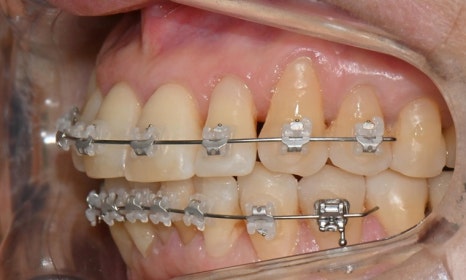

치료 2개월 후

치료 2개월 후 환자분께서 가장 고치고 싶어하셨던 오른쪽 앞니가 벌써 배열이 가지런하게 변한 것을 확인할 수 있습니다.